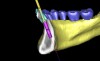

Following the first goal of orthodontia—moving tooth No. 22 to a proper functional and anatomical position—a periodontal reevaluation was performed, demonstrating an improvement in short- and long-term tooth prognosis. At this time, the decision was made to abort continual extrusion of teeth Nos. 21 and 22, although some attachment level discrepancy remained between Nos. 21 and 22 (Figure 14). Implant diagnostics ensued and included mounted study models and a diagnostic wax-up. A scanning appliance was created to demonstrate the desired prosthetic outcome requirements, and the patient was referred for computed tomography (CT) scans. CT scan assessment demonstrated successful orthodontically directed GBR to allow implant placement (Figure 15 and Figure 16). Only minor GBR therapy would be needed and could be accomplished simultaneously with implant installation. Guided implant placement occurred, using an open flap approach (Figure 17). During surgery, root dehiscences were noted on teeth Nos. 21, 22, 24, and 25, as well as the anticipated dehiscence following implant placement at No. 23 (Figure 18). A positioning reference (index) was secured after implant placement to facilitate a provisional prosthesis at stage II surgery. Cortical perforations then were placed adjacent to the implant to encourage angiogenesis (Figure 18), and mineralized freeze-dried bone allograft enhanced with platelet-derived growth factor was placed over the dehiscences for purposes of guided tissue regeneration and GBR (Figure 19). A highly resorbable collagen membrane was placed to stabilize the allograft. The flap was coronally repositioned, and primary-intention wound healing was achieved (Figure 20 and Figure 21). Following 4 months of stage I surgery, implant uncovery and immediate provisionalization were performed in conjunction with connective tissue grafting. Final orthodontic tooth movement then ensued, using the implant as anchorage to optimize end-tooth movements, interroot separation, and the cuspid-protected occlusal scheme. A final impression then was secured, and a zirconia abutment (Figure 22) with an all-ceramic restoration was fabricated for the prosthetic phase completion of No. 23 (Figure 23 through Figure 25).